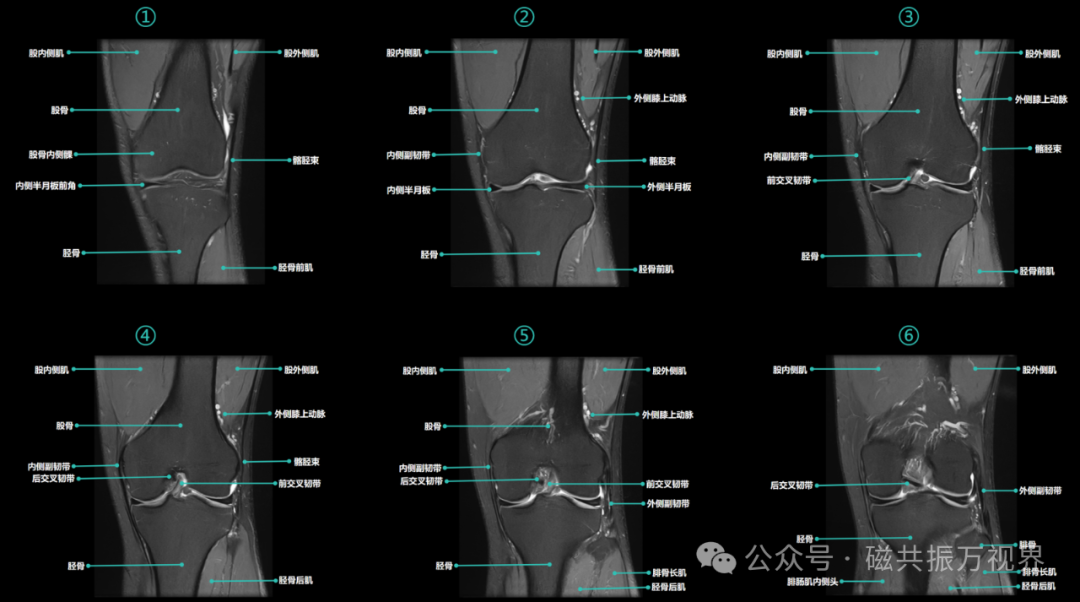

2)矢状位(自内向外)

前交叉韧带起自胫骨髁间棘前方,斜向后外上走行,止于股骨外侧髁内侧面。后交叉韧带起自胫骨髁间棘后方,斜向前内上走行,止于股骨内侧髁内侧面(斜十字相交,如图④)。